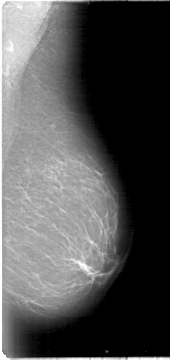

D_4009_1.RIGHT_CC

LEFT_CC LINES 5071 PIXELS_PER_LINE 2401 BITS_PER_PIXEL 12 RESOLUTION 43.5 NON_OVERLAY